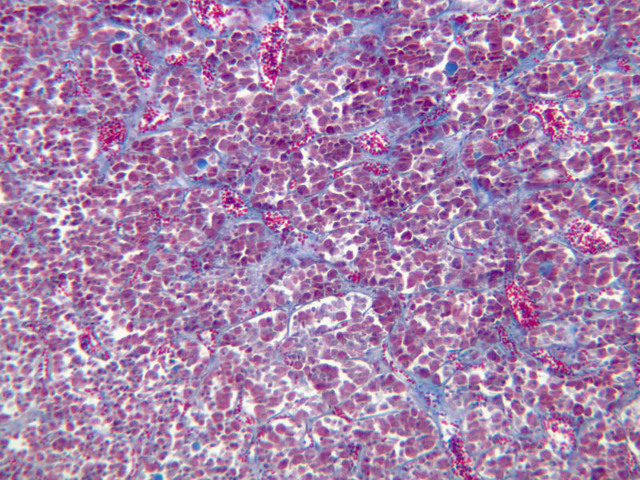

The medulla is composed of large epithelioid cells, arranged in small groups or cords which are separated by blood vessels. Usually, several large veins mark the center of the medulla. When fresh adrenal gland is incubated in solutions of chromium salts (as was the specimen on slide B-61), brownish precipitates form in the cells of the medulla-- hence, the name chromaffin cell (B-61, chromaffin [2.5x, 10x, 20x, 40x] [2.5x, 10x, 20x, 40x-labeled]). The more darkly stained chromaffin cells are known to contain norepinephrine, the less darkly stained cells, epinephrine. In essence, chromaffin cells are specialized postganglionic sympathetic neurons. How does the ultrastructure of these cells differ from that of the secretory cells of the adrenal cortex?